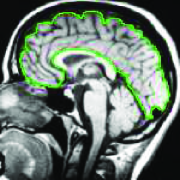

Metrication error: Metrication error, also known as grid bias, is defined as the artifacts which appear in graph-based segmentation methods due to penalizing region boundaries only across axis aligned edges. ¡ltx:note¿Figure 3 compares the discrete and continuous version of a max-flow algorithm. As seen in Figure 3, the contours obtained by graph cuts are noticeably blocky in the areas with weak regional cues (weak data term), while the contours obtained by the continuous method are smooth.¡/ltx:note¿ The discrete nature of graph-based methods makes it difficult to efficiently implement a convex regularizer like total variation in the discrete domain. Metrication error can be reduced in graph-based methods by increasing the graph connectivity, e.g. (Boykov and Kolmogorov, 2003), but that also increases memory usage and computation time. In contrast, within the continuous domain, there is no such limitation and regularizers can be implemented efficiently that makes the PDE approaches free from metrication error. Note that although approaches with continuous energy formulations do not induce metrication errors, due to the discrete nature of digital images, all continuous operations are estimated by their discrete versions in the implementation stage.

(a) GF

(b) CCMF

(c)

(d)

(e)

(f) Figure 3: ¡ltx:note¿Metrication artifacts. Brain segmentation using (a) classical max-flow algorithm or graph cuts (GC) and (b) combinatorial continuous max-flow (CCMF) (Couprie et al., 2011). (c,e) Zoomed regions of (a). (d,f) Zoomed regions of (b).

(Images adopted from (Couprie et al., 2011))¡/ltx:note¿ -